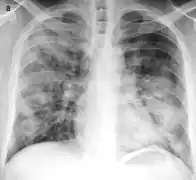

Placa posteroanterior de tórax en el sujeto normal.